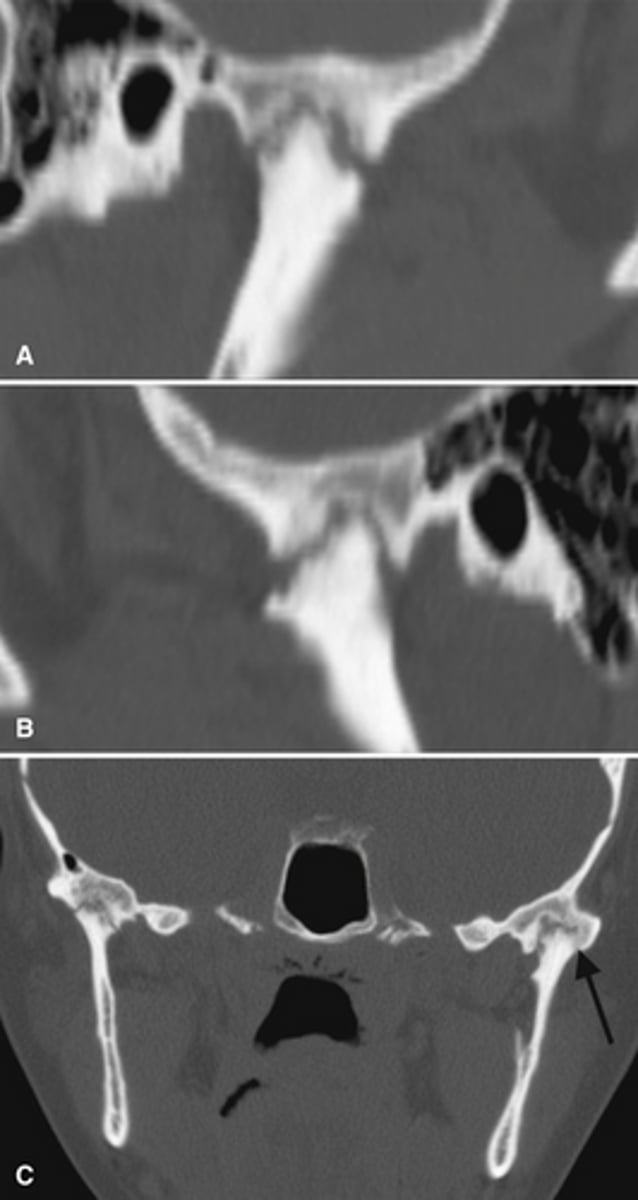

Coronoid hyperplasia

- Elongation of the coronoid process where the tip extends 1cm above the inferior rim of the zygomatic arch

- Usually bilateral

- The condyle can hit the posterior of the maxilla or the zygomatic bone during opening and restrict condylar translation.

What is this developmental abnormality, and what is the etiology for it?

What is this developmental abnormality?